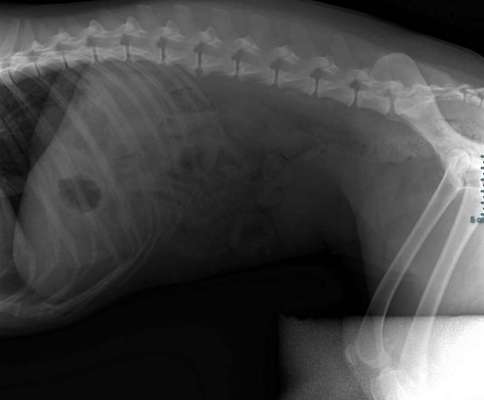

Seitliche Aufnahme mit spondylose

Anhand des Röntgenbildes (ich bin keine anerkannte geprüfte Expertin) handelt es sich um eine fortgeschrittene Dysplasie des rechten Hüftgelenks. Ist das Video unter Medikamentengabe entstanden oder von vorher?

Vermutlich kann sie die Fehlstellung der Hüfte mithilfe ihrer Muskulatur noch gut kompensieren. Mit zunehmendem (altersbedingtem) Schwund der Muskulatur kann sich eine Verschlechterung des Gangbildes einstellen. Zusätzliche Arthrosen des betroffenen Gelenks durch den chronischen Reiz können zusätzlich die Beweglichkeit einschränken und zu vermehrter Schmerzhaftigkeit führen.